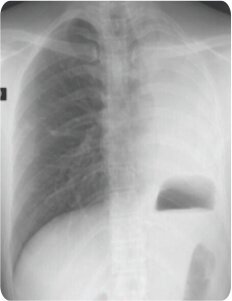

Radiological improvement was seen on X-ray 24 hrs post procedure.

Post Procedure